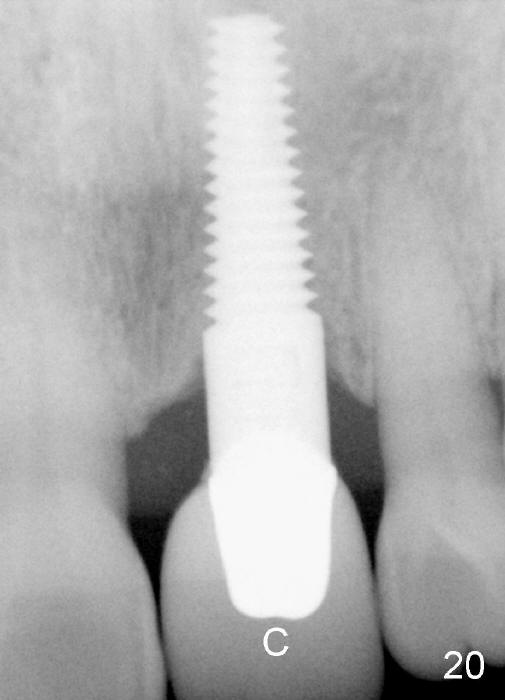

A 60-year-old lady had an abscess mesial to #9 six years ago (Fig.1,2 <), treated as a perio lesion by laser (Fig.3) and osseous surgery without bone graft (Fig.6, followed by CT exam revealing semi-circumferential bone loss (Fig.4,5). When the perio treatment failed, attention was paid to endo aspect (Fig.7-9). In fact the pulp was found to be vital when access to root canal therapy was made. As expected, the treatment failed again. The palatal fistula persisted. The infection was suspected to be a source of remote immediate implant site (#30). The tooth #9 was extracted. It appears that there is a semilunar crack line in the linguomesial root (Fig.12). When the socket healed 2 weeks post extraction (Fig.10), the #30 buccal defect was debrided with bone graft. There was no bone resorption 4 weeks post extraction (Fig.11); a 4.5x17 mm implant was placed (Fig.13-15). An immediate provisional was fabricated (Fig.16-18). Fig.19,20 were taken 3 months post implantation and 7 months post cementation, respectively. Dense bone forms around the implant coronally 4 years 5 months post cementation (Fig.21), while the gingiva is healthy palatally (Fig.22) and buccally (Fig.23).